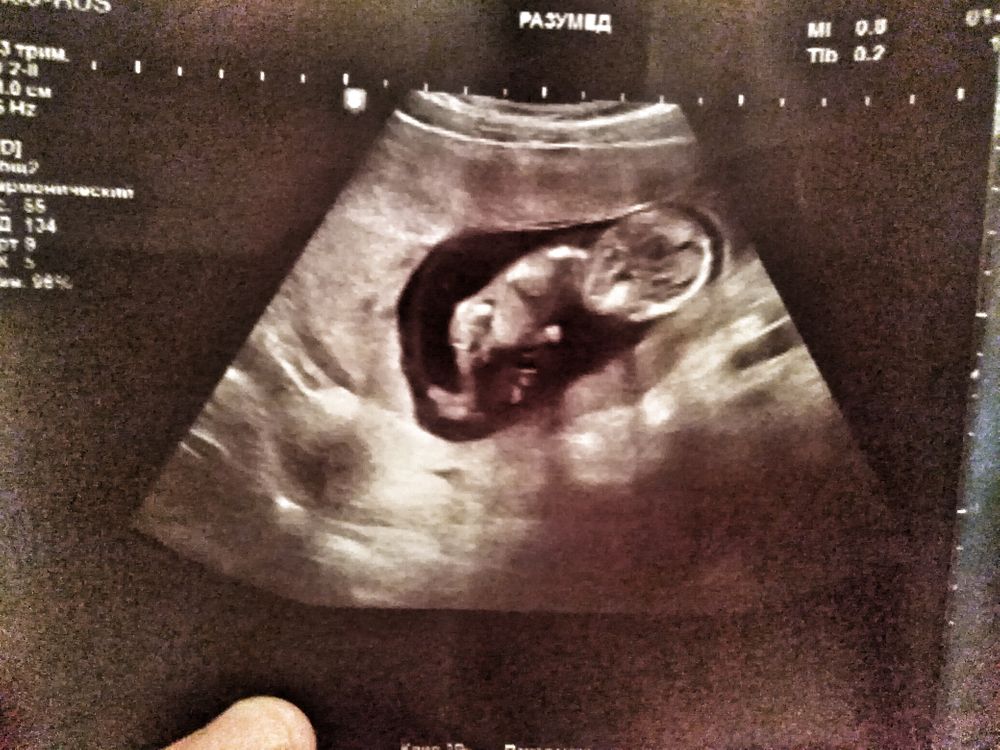

Смотреть на фото малышей с УЗИ😍 это отдельный вид кайфа🥰🤗, я 4 июля иду на 1й скрининг, будет 12-13 недель, беру мужа😁, в надежде может вдвоём что рассмотрим)) Ну, хотя бы свою интуицию проверим🙈. Имя придумали уже много лет назад и для девочки и для мальчика😁, ждем Каждого с любовью❤🙏 Но так интересно КТО , прям очееень)))

Моя интуиция я пока так чувствую, что мальчик, но нет точной уверенности как с 1м ребёнком) Там сомнений у меня не было вообще никаких, хотя реально пол узнали толькт в 22 недели на 2м скрининге🤩😊